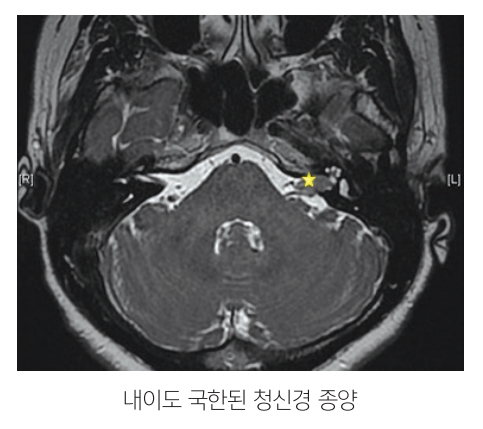

MRI 검사에서 돌발성 난청 환자의 0.8-3%에서 청신경종양이 발견되는데, 청신경 종양은 소뇌교각에 생기는 가장 흔한 양성종양으로 두개내 종양의 약 8%를 차지하며 서서히 진행하는 감각신경성 난청과 이명, 어지럼, 안면 감각의 이상이나 결막반사의 소실 등의 증상으로 나타나나, 약 20% 정도의 환자에게서는 돌발성 난청이 증상으로 발현된다. 종양의 기원은 대개 전정신경의 신경초에서 생기며 주변의 혈관, 신경을 직접 침범하기보다는 서서히 누르면서 인접 신경의 기능에 장애를 주게 된다. 신경섬유종증과 동반되기도 하며, 제2형 신경섬유종증은 양측성 청신경종양이 발생한다. 종양의 크기는 내이도(Internal auditory canal)에 국한된 종양에서부터 소뇌교각(cerebellopontile angle)으로 확장된 종양 등 다양하며, 크기, 위치, 환자의 나이, 청력의 상태 등에 따라 수술적 치료, 감마나이프를 이용한 방사선 치료, 정기적인 추적관찰 등으로 치료가 이루어진다.